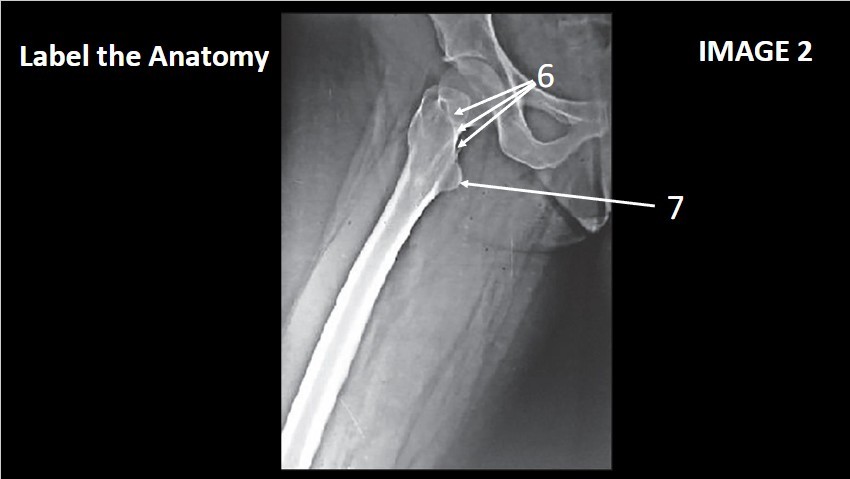

6

intertrochanter Crest

7

Lesser trochanter